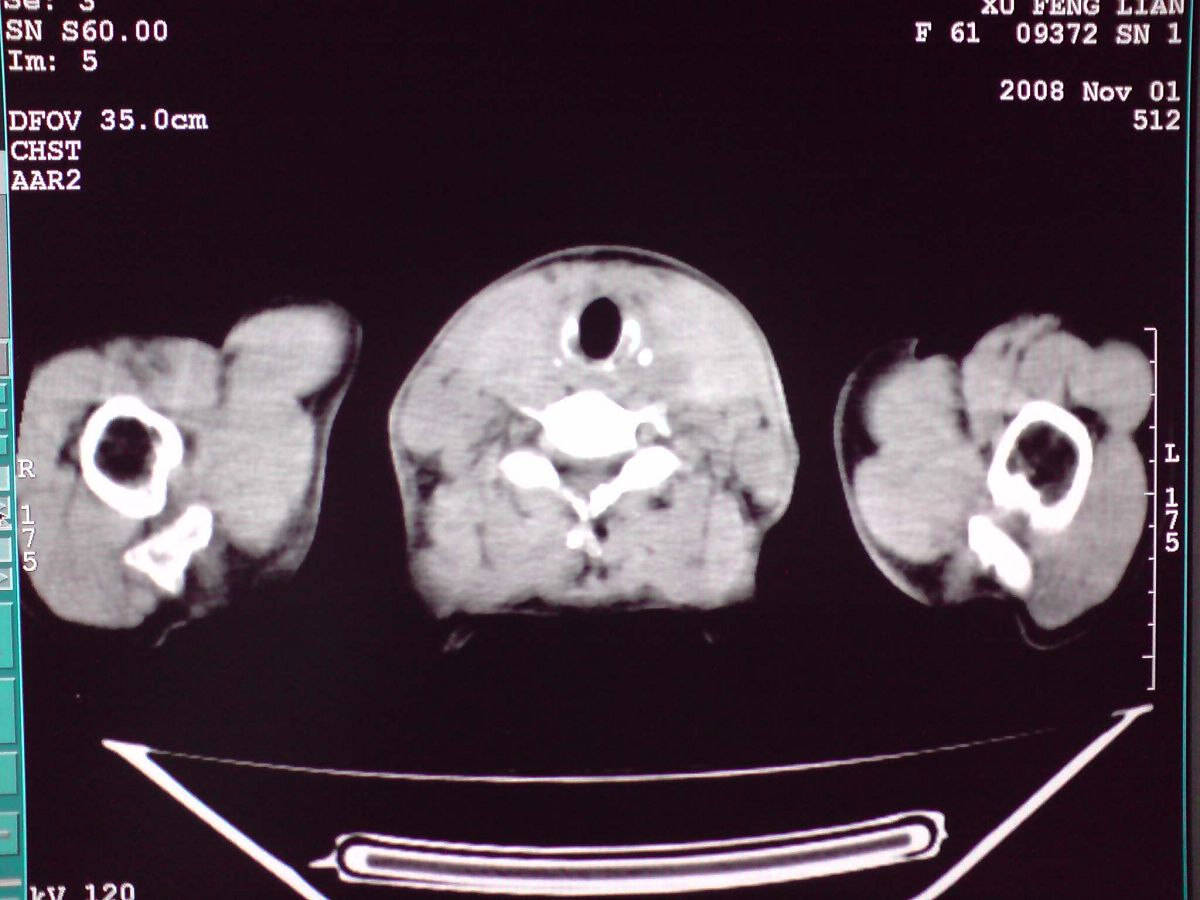

患者女性,65岁,无明显不适,甲状腺功能无异常

结节状甲状腺肿,部分突入胸腔,形成胸内甲状腺

胸内甲状腺伴结节性甲状腺肿!因病灶明显钙化很难排除:甲状腺癌可能性!建议穿刺活检!

双侧甲状腺肿大,向下部分突入胸腔,双侧甲状腺内密度不均,可见结节状低密度影,并见散在斑点状钙化,增强后病灶实性部分强化明显,气管受压稍变窄左移。

考虑:双侧甲状腺腺瘤可能,不除外甲状腺癌。

甲状腺左右叶增大,并向下突入胸腔内,其内可见多发条片状钙化影及囊性低密度影,邻近组织及血管无浸润、包埋征像,双侧结节性甲状腺肿伴右侧甲状腺腺瘤形成可能性大,甲状腺癌待排;因病人就要手术,期待结果。